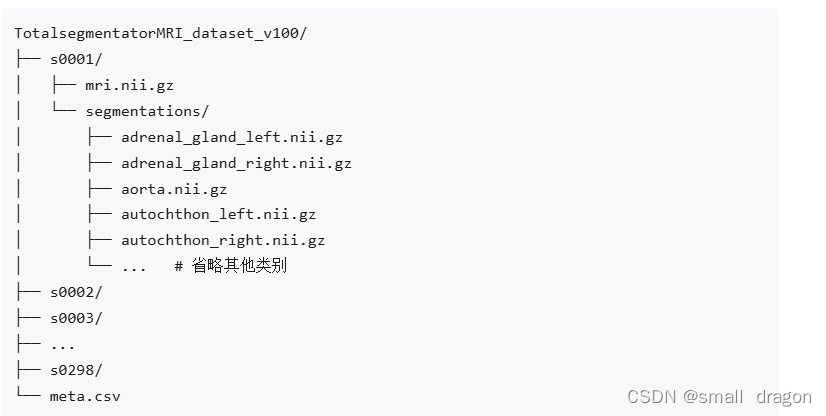

文件列表

数据集包含了 298 例 MR 图像,并提供多达 56 种不同常用解剖结构的分割标注。其中,251 例 MR 图像来自 2011 年至 2023 年间巴塞尔大学医院的图像存档和通信系统(PACS),另外 47 例 MR 图像来自影像数据共享平台(Imaging Data Commons,IDC),以增加图像的多样性。该数据集源自日常临床工作中的随机抽样,代表了一个可推广到临床应用的真实世界数据集。它涵盖了各种不同的病变、扫描仪、成像序列和来自不同医疗机构的数据。值得注意的是,尽管官方论文提到包含 59 种类别,但公开的数据集中仅提供 56 类标注,略有差异。